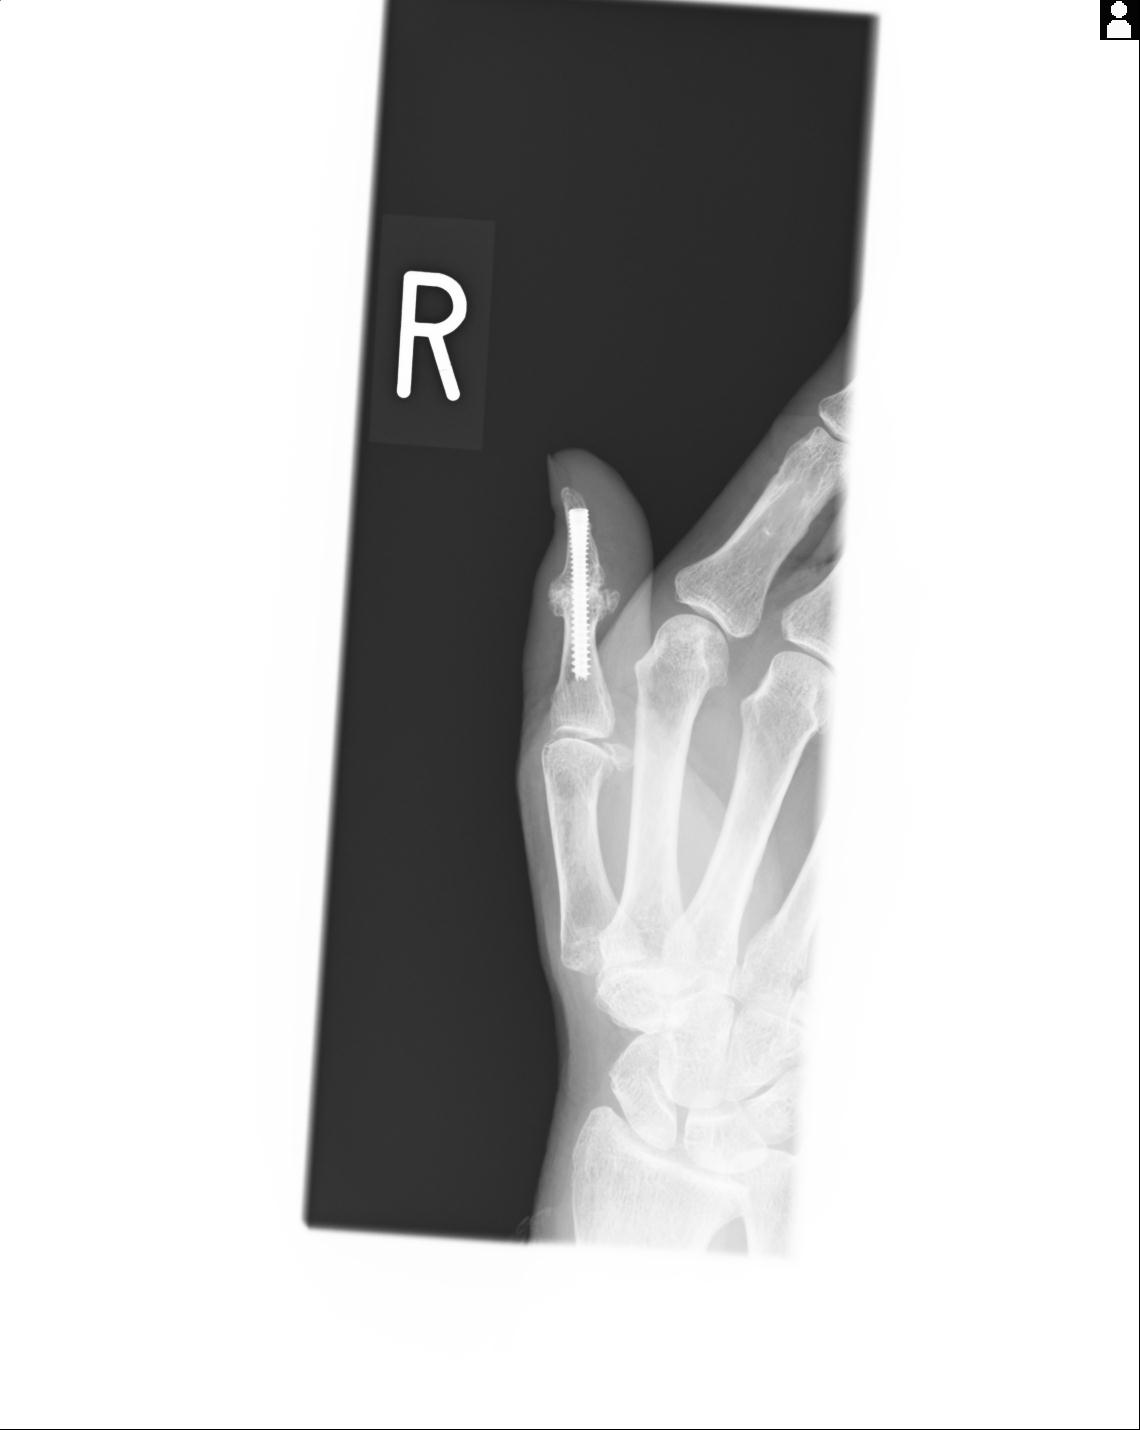

20857 1/11 左手 3R 1/19 4R 55歳男性 小指中節骨骨折